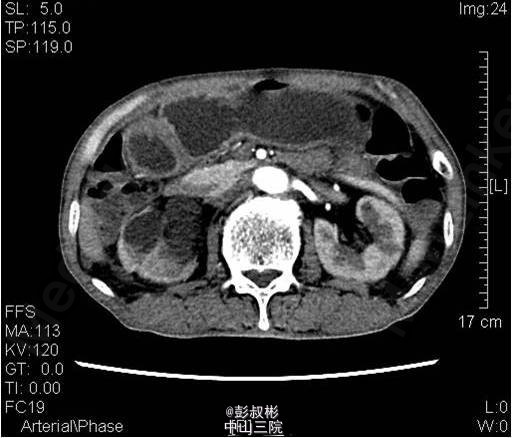

3、既往病史:既往“高血压”病史20年余,自服硝苯地平。“脑梗死”病史半年余,规律服用抗凝药物。 4、入院查体:无明显阳性体征。 实验室检查: 2015-01-11 肌酐101.2umol/L 。 2015-01-13总前列腺特异性抗原1.1ng/ml,游离前列腺特异性抗原0.3ng/ml。 2015-01-15 白细胞总数3.21x10E9/L,红细胞总数2.61x10E12/L,血红蛋白浓度78g/L,肌酐131umol/L ,白蛋白27g/L。 影像学检查: 2014-12-30心电图:完全性右束支传导阻滞。 2014-12-30全腹螺旋CT 检查所见:1、前列腺增生并钙化,建议MRI增强进一步检查除外合并肿瘤性病变。2、右侧盂管交界处结石并重度梗阻性肾积水,右肾结石;左肾多发钙化灶;左肾多发囊肿。3、慢性胆囊炎。4、双肺下叶多发小结节。 2015-01-14核素肾动态显像+GFR双血浆测定:右肾灌注、功能重度受损。左肾灌注正常,功能中度降低。肾小球滤过率:左肾为23.4ml/min,右肾为9.0ml/min。 2015-01-15彩超心脏:二尖瓣反流(轻度)。三尖瓣反流(轻度)。左室收缩功能正常。左室舒张功能减退。